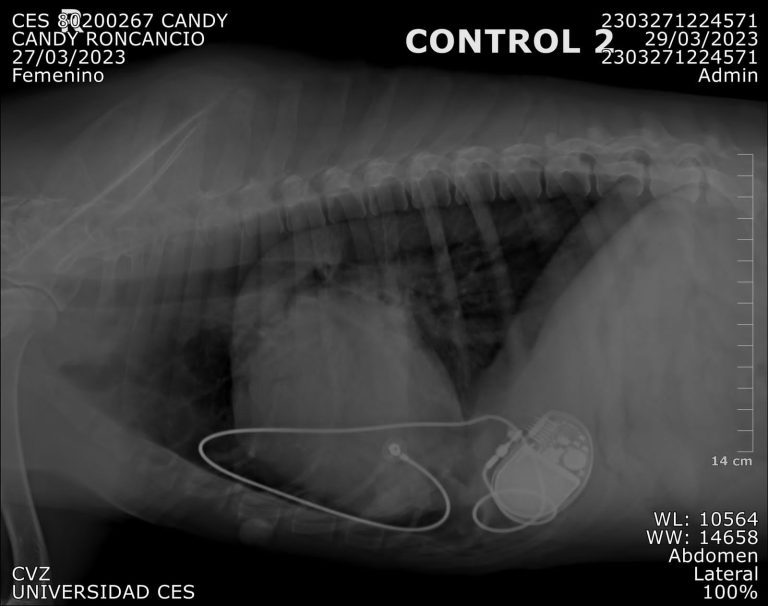

Se trata de Candy, una perrita criolla proveniente de Bogotá. Con 10 años, ella fue diagnosticada con arritmia. Fue remitida al Centro de Veterinaria y Zootecnia de la Universidad CES en Medellín, tras conocer la exitosa cirugía que se le practicó a Romeo, un gato de raza Maine Coon, la primera especie en su tipo que recibió el dispositivo en el país y hoy está en buen estado de salud. Candy es el primer canino que recibe el marcapasos de parte de la Universidad, pero no es el único en el país.

Veterinarios en Bogotá y Medellín le diagnosticaron a Candy una arritmia, que consiste en un bloqueo atrioventricular de tercer grado. Esta cardiopatía le generaba constantes desmayos e inactividad, toda vez que al interior de su cuerpo el corazón crecía por esta causa. Por esa razón, los profesionales en salud animal optaron por el implante de marcapasos.

“La cirugía que le practicamos en el CVZ – CES fue un implante de marcapasos ¿En qué consiste? Es poner un electrodo en el ventrículo izquierdo. Lo que hace el electrodo es que el ventrículo se contraiga a la frecuencia de los atrios. Ahora ya no se contrae en 20 latidos como estaba Candy, sino que se programó en un rango entre 80 y 150 latidos por minuto”, explicó la Dra. Maria Adelaida Mejía, médica veterinaria y coordinadora de Área de Cardiología en el Centro de Veterinaria y Zootecnia de la Universidad CES.